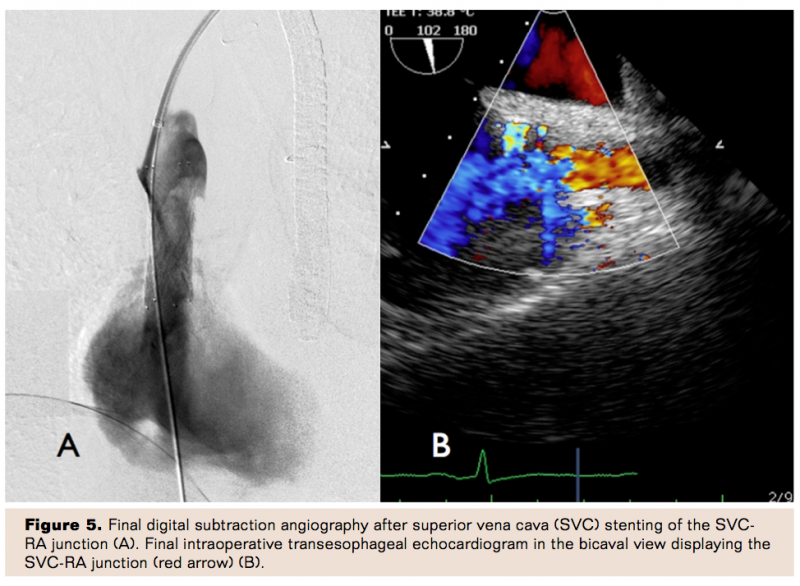

Ultimately, a 14.0 mm x 40 mm self-expanding Protege stent (Covidien) was positioned fluoroscopically across the stenosis. The stent was positioned precisely at the right atrial junction without protrusion into the atrium as confirmed by TEE (Figure 3B). After optimal positioning, the stent was deployed and postdilated with a 12.0 mm x 20 mm FoxCross balloon (Abbott Vascular) (Figure 4). Final angiography and echocardiography (Figure 5) revealed excellent stent expansion with complete resolution of the resting pressure gradient. Intra-procedural hemodynamics revealed a decrease in central venous pressure from 14 mm Hg to 6 mm Hg following stent deployment and postdilatation. Subsequently, new pacing leads were placed using the right subclavian approach. At 4 months’ follow-up, the patient was asymptomatic with complete resolution of the SVC syndrome.